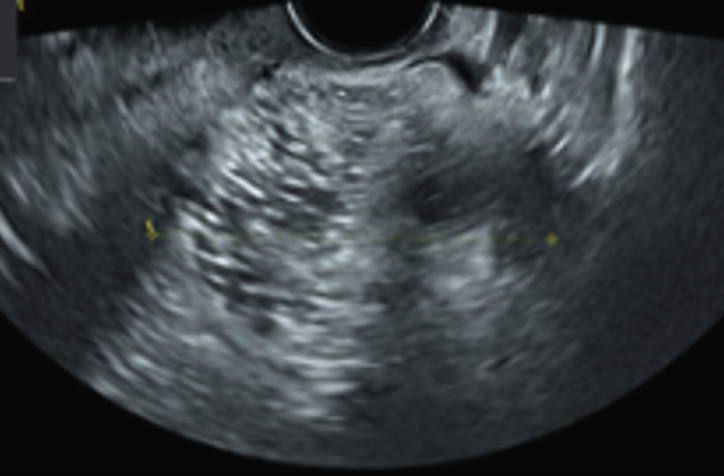

Guida al Counselling di Settembre 2025: teratoma cistico maturo

vi presentiamo la guida al counseling di Settemnbre 2025 sul teratoma cistico maturo